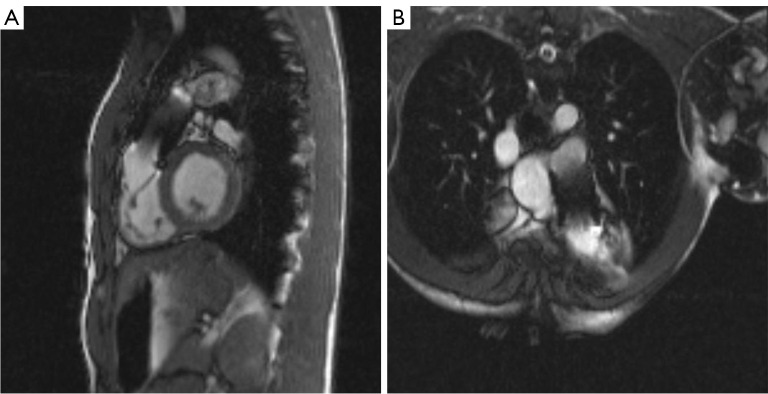

瓣膜性心脏病(vhd)需要明确解剖结构、严重程度和风险分层,以最好地确定手术需求、干预类型和连续随访。先天性病变是非常罕见的,往往与更复杂的病变。在非侵入性成像方式中,心血管磁共振(CMR)是全面评估和量化vhd的基本工具。CMR可以提供广泛的心脏和心脏外结构在任何平面上的解剖视图,流量和体积量化,以及心室重构和活力的信息。在瓣膜狭窄的情况下,CMR的量化主要基于最大瓣膜开度时的阀口直接测量,尽管由于时间分辨率降低,CMR数据仍然不如标准超声心动图可靠。通过CMR对大血管解剖的定义可以区分瓣膜、瓣膜下或瓣膜上病变。对于瓣膜反流,CMR是量化心室容积和功能的金标准,也是通过平面相对比成像直接计算半月瓣反流的金标准。额外的流量测量可以集成来交叉检查大血管流量和冲程体积的定量数据。CMR研究建议采用标准化方法。最小的CMR数据集应该包括二维电影和相衬序列,以及三维全心成像。这应应用于临床实践,以评估vhd,包括最复杂的先天性病变。

Valvular heart diseases (VHDs) require definition of anatomy, severity, and risk stratification to best define procedural need, type of intervention and seriate follow-up. Congenital lesions are much rarer and often associated with more complex lesions. Among noninvasive imaging modalities, cardiovascular magnetic resonance (CMR) represents a fundamental tool for complete assessment and quantification of VHDs. CMR can provide wide anatomical views on cardiac and extra-cardiac structures in any plane orientation, flow and volume quantification, as well as information on ventricular remodeling and viability. In the context of valve stenosis, quantification by CMR is based primarily on direct measurement of valve orifice at maximal valve opening, although CMR data remain less reliable than standard echocardiography due to reduced temporal resolution. Definition of great vessels anatomy by CMR can allow differentiation of valvular, subvalvular or supravalvular lesions. For valve regurgitation, CMR is the gold standard for quantification of ventricular volumes and function and for direct calculation of regurgitation of the semilunar valves with through-plane phase-contrast images. Additional flow measurements can be integrated to cross-check quantitative data on great vessels flow and stroke volumes. A standardized approach is recommended in CMR studies. A minimum CMR dataset should include two-dimensional cine and phase-contrast sequences, and three-dimensional whole heart imaging. This should be applied in the clinical practice to assess VHDs, including most complex congenital lesions.